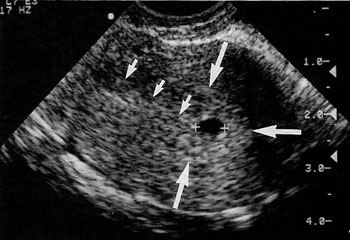

Εικόνα 3α. Αληθής εμβρυϊκός

σάκος. Ενδομήτριο (μικρά βέλη). Διπλή ηχητική απεικόνιση του περιγράμματος του

σάκου, που οφείλεται στον ηχητικό διαχωρισμό του αληθούς φθαρτού από το ανεστραμμένο

(μεγάλα βέλη). Ο σάκος εμφανίζεται σαν κάτι ξεχωριστό στο ενδομήτριο. β. Ψευδοσάκος.

Ενδομήτριο (μικρά βέλη), φθαρτοειδής αντίδραση (μεγάλα βέλη). Ο σάκος αποτελεί

συνέχεια του ενδομητρίου.

ΨΕΥΔΗ

ΑΡΝΗΤΙΚΑ ΥΠΕΡΗΧΟΓΡΑΦΙΚΑ ΣΗΜΕΙΑ

Σάκοι ψευδοκύησης

Ο σάκος ψευδοκύησης ορίζεται ως ένας σάκος με ενδομήτριο υγρό, που δεν περιβάλλεται

από διπλό φθαρτοειδή δακτύλιο ή δεν περιέχει λεκιθικό σάκο, ενώ ανευρίσκε σε

8% έως 29% των περιπτώσεων με εξωμήτρια κύηση (εικόνα 3). Η επισήμανση του σημείου

διπλού φθαρτοειδούς σάκου ή εμβρυϊκής ανάπτυξης, βοηθά συχνά στη διάκριση των

σάκων ψευδοκύησης από κανονικούς ενδομήτριους σάκους κύησης, αλλά μπορεί να

αποδειχθεί προβληματική στη διαφορική διάγνωση μεταξύ σάκων ψευδοκύησης και

παλίνδρομης κύησης, κατά τις πρώτες εβδομάδες.(22-23)